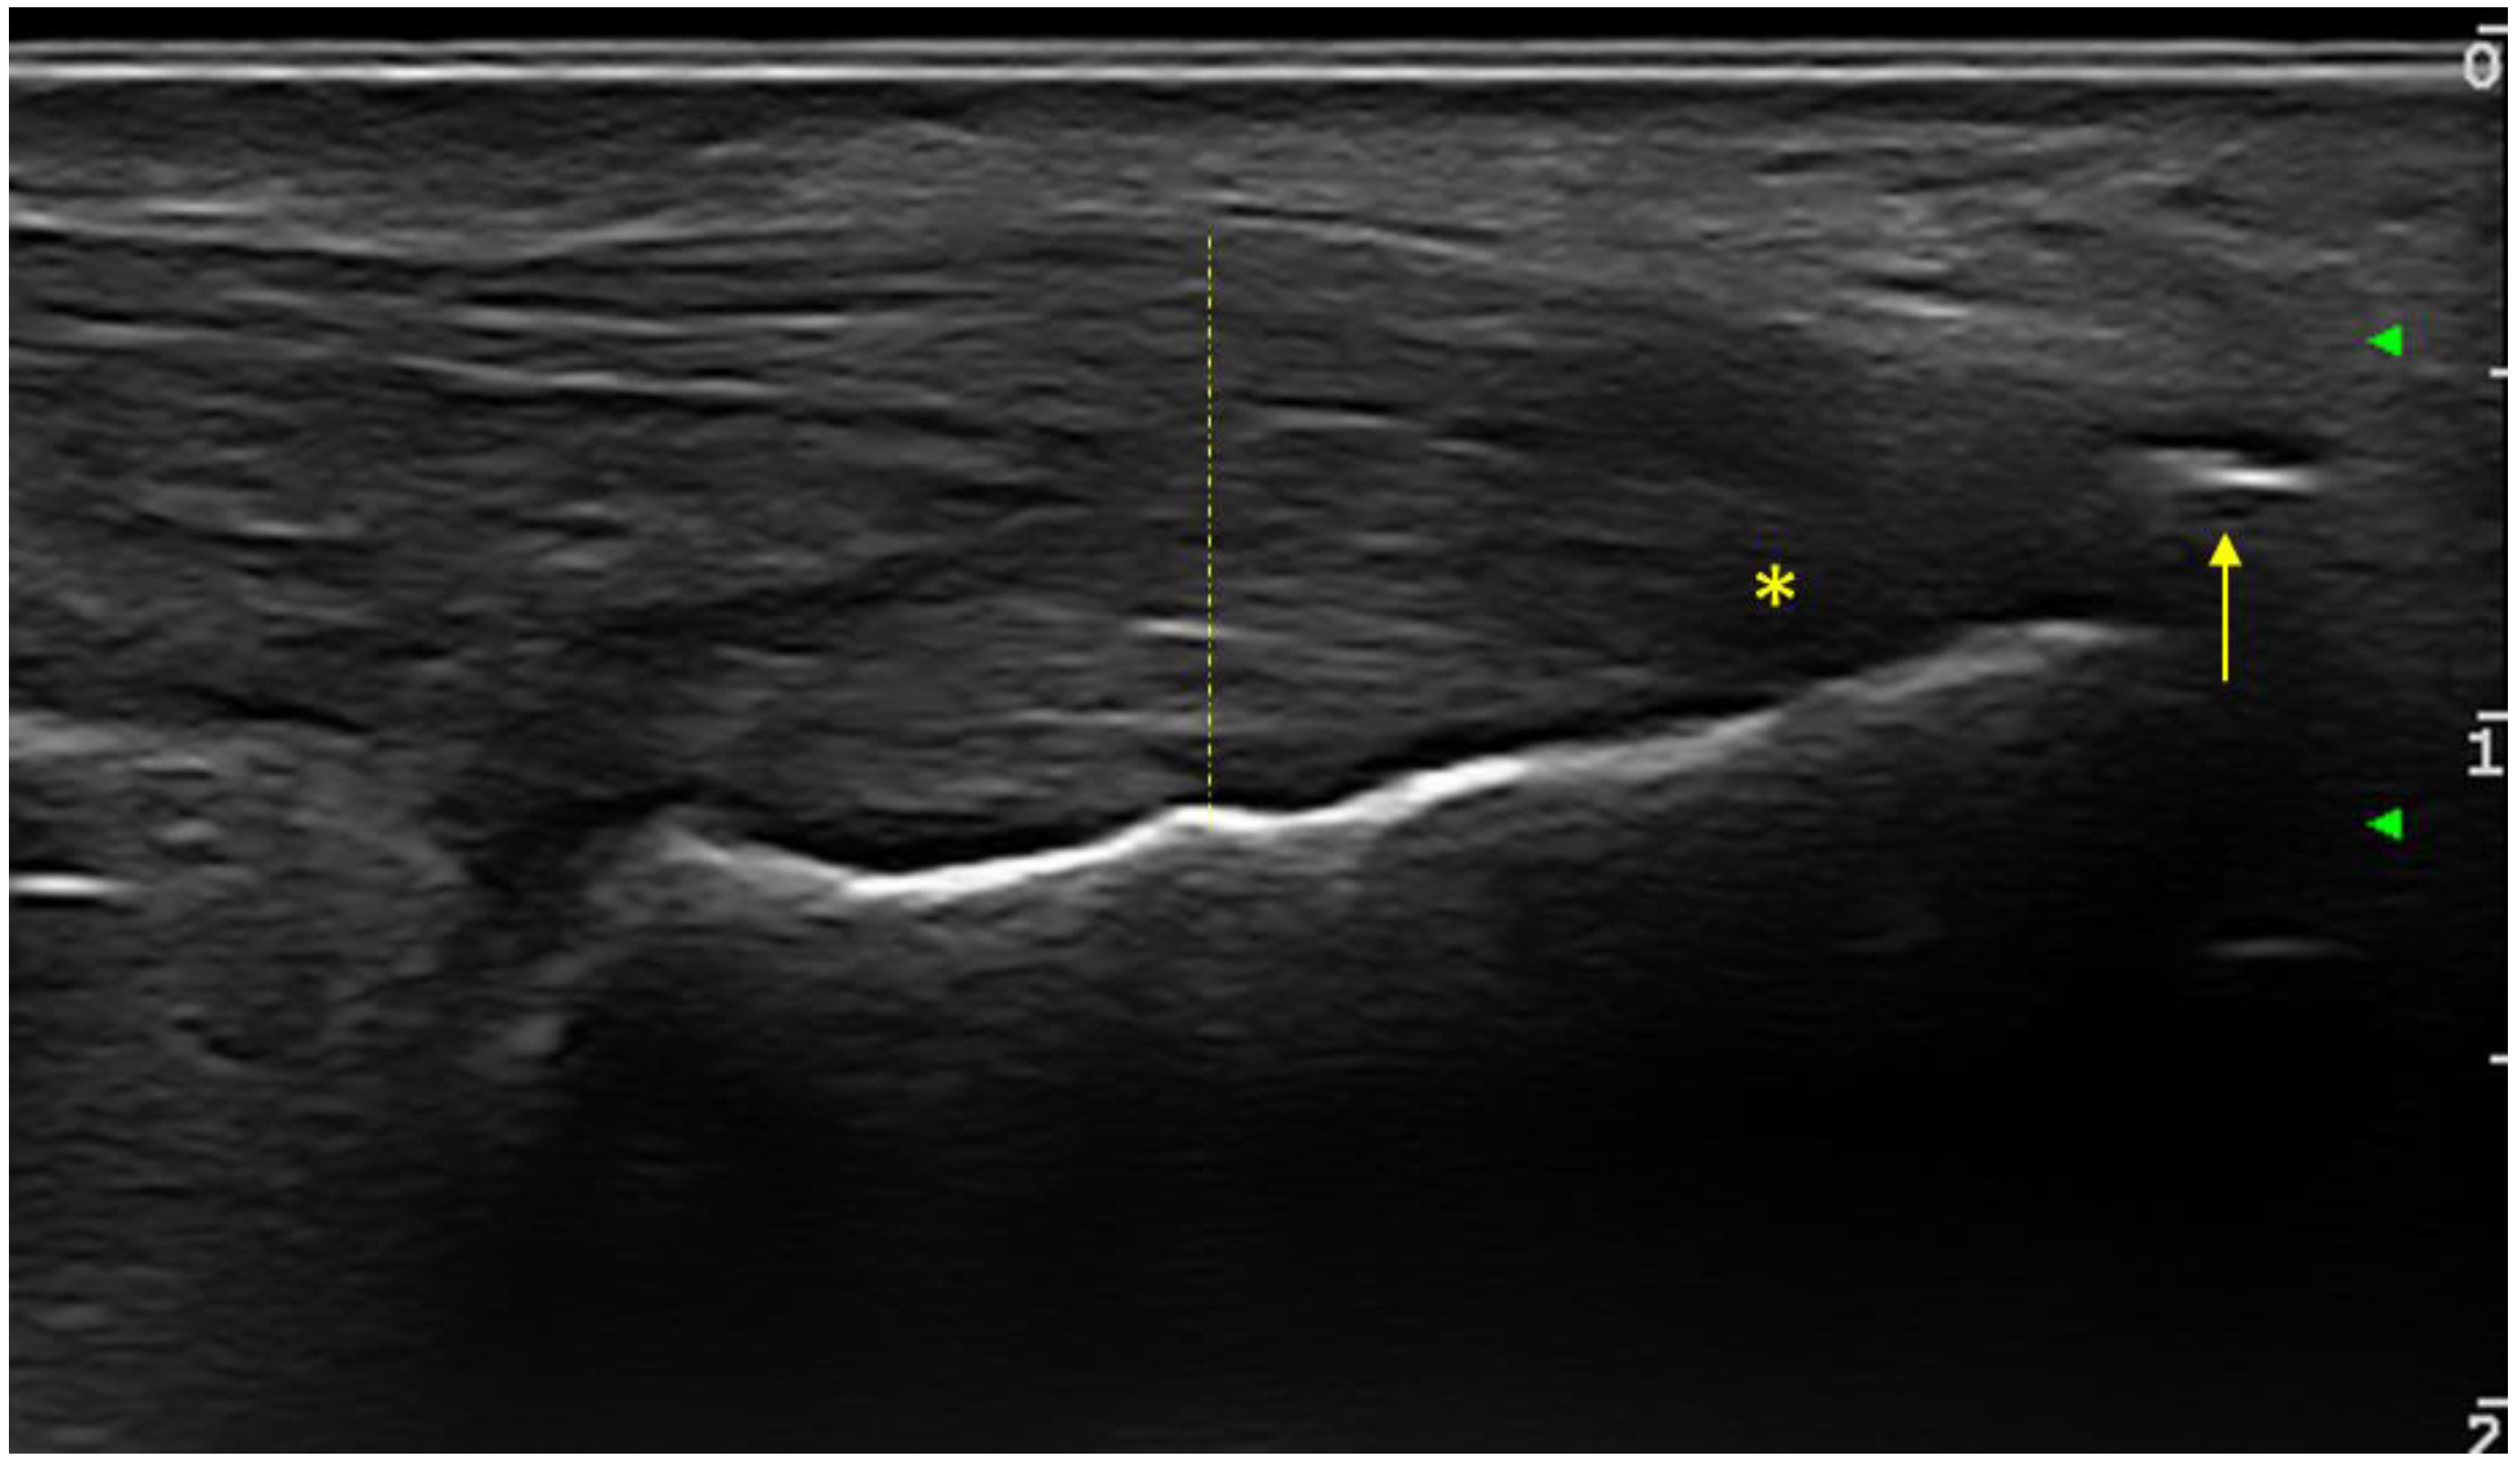

The following entheses were evaluated bilaterally in transverse and longitudinal sections: supraspinatus tendons, common extensor digitorum tendon, common digitorum flexor tendon, triceps tendon, quadriceps tendon, proximal and distal patellar tendon, Achilles tendon and plantar fascia. At each individual enthesis, the presence or absence of the following elements was evaluated: thickening, hypoechogenicity, calcifications/enthesophytes, erosions and the PD signal. The evaluated entheses allowed for the calculation of the Glasgow Ultrasound Enthesitis Scoring System (GUESS) [24], Madrid Sonographic Enthesitis Index (MASEI) [25] and Belgrade Ultrasound Enthesitis Score (BUSES) [26] sonographic enthesitis scores, in order to assess the discriminative capacity between the two groups of patients. For all examined entheses (upper and lower limb), the presence or absence of any of the evaluated changes (hypoechogneicity, increased thickness, calcifications/enthesitis, bursitis, or PD signal) was bilaterally noted. At the level of the lower limb, the elementary changes in the OMERACT definition of enthesitis were included (Figure 1).

Figure 1. Longitudinal ultrasound scan of Achilles tendon OMERACT-defined enthesitis at calcaneus insertion in a PsA patient (grayscale examination): hypoechoic aspect (star), thickness increase (dashed line) and the presence of enthesophytes (arrow).